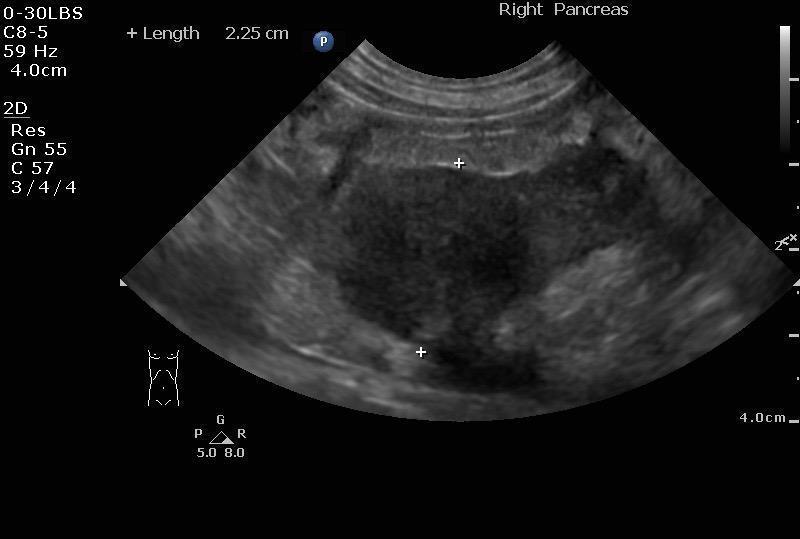

Pancreatic lymphoma confirmed with cytology in a 10 year old MN DSH cat

A 10-year-old MN DSH was presented for evaluation of decreased appetite and lethargy. Abdominal effusion was present on physical examination. Serum biochemistry showed azotemia.

Pancreatic lymphoma

FNA revealed cellularity is high consisting predominantly of large immature lymphoid cells admixed with a few small lymphocytes and blood. The cells have a small to moderate amount of basophilic cytoplasm often with small discrete vacuoles. The nuclei are round with nucleoli. Microscopic Findings: Lymphoma. The predominance of lymphoblasts is consistent with lymphoma.

Pancreatic mass, suspect carcinoma, carcinomatosis. I recommend cytology assessment +/ cytospin of the free fluid and culture if a definitive diagnosis is not obtained. There was no overt evidence of organ metastasis noted; however, omental seeding and metastasis is suspected.

Image Interpretation

The right pancreatic base revealed a 2.25 x 3.0 cm mass with irregular, nodular, ill defined surrounding changes throughout the omentum. Ultrasound-guided FNA was performed without complication. The mass appeared to be adhered to the duodenum.